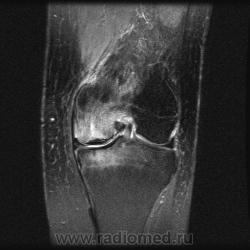

Сразу скажу, что следующим этапом было выполнение исследования МРТ, которое я представлю позднее.

Итак, было выполнено исследование МРТ, которое показало асептический некроз медиального мыщелка бедренной кости и медиального мыщелка большеберцовой кости Также имеются дегенеративные изменения в заднем роге медиального мениска. Передняя и задняя крестообразные связки не повреждены.

Признаться, я и сам удивился несоответствию рентгенологической картины тому, что мы увидели на МРТ (относительно костных структур).

По поводу асептического некроза сразу двух костей -это лишь мое предположение, т.к. я сам встречался, в том числе, в литературе с асептическим некрозом только одной кости, как правило, мыщелка бедренной кости. Но как же тогда объяснить субхондральные изменения и отек большеберцовой кости?

Глядя на магниторезонансные томограммы, вижу: гвоздь проблемы именно во внутреннем мыщелке бедра. Но, чтобы интерпретировать и, по возможности объяснить картину нам отсталым, нужен иной опыт и знания. Надо звать магниторадиологов.

кроме упомянутых измемений, также отмечается повышение МР-сигнала в заднем рожке медиального мениска - трещина?

Представленные изменения стоит расценивать как результат хронической травматизации мыщелка , вследствие частичной дислокации медиального мениска. Дифференцировать между спонтанным остеонекрозом мыщелка (что чаще встречается в пожилом возрасте) и рассекающим остеохондритом. В любой литературе по МРТ коленного сустава эта патология описана достаточно подробно. Вот у питерских авторов точно описана.

Мне встречались , даже пару раз некрозы медиальных мыщелков обоих костей , в этом случае как правило мениск за пределами суставных поверхностей.

имею не очень большой опыт в ортопедии.., но не думаю что это следует называть некрозом... во всяком случая про большеберцовую кость.

просто выраженный отек костного мозга на фоне травмы мыщелков

Может дело в повреждении гиалинового хряща суставной поверхности , а не в мениске вовсе. Хрящ истончается, повреждается от нагрузки, а потом и кость....

но все равно такой выраженный отек мыщелка бедренной кости видел только после острой травмы, которое не исключается наличием хронического махрового процесса....